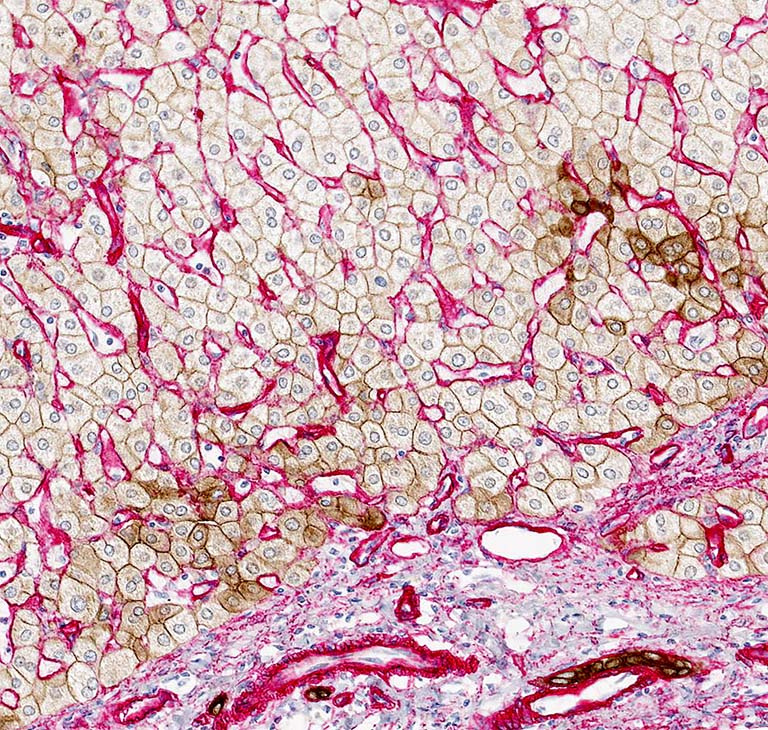

This image shows a section through a human liver biopsy demonstrating hepatocytes (light brown) and bile duct cells (dark brown) as well as collagen IV (red), a type of collagen primarily found in the basement membrane, a thin, fibrous membrane that separates epithelial and endothelial cells from the surrounding connective tissue.